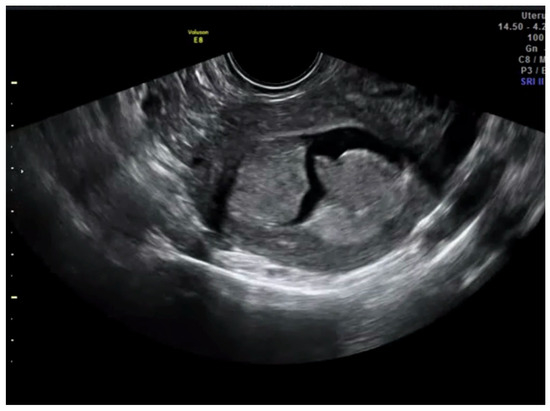

After this, each trainee had to visualize 45 videoclips of TVS assessment of the uterus from cases of endometrial cancer already treated surgically. The number of 45 videoclips was set arbitrarily. All real-time examinations and videoclip recordings had been performed by the trainer. Doppler assessment was not included in the videoclip. Videoclips were randomly selected by the trainer from the Department imaging database. The ratio of cases with <50% and ≥50% of myometrial infiltration was 4:1. The machine settings that were used were standard ones; they included the use of harmonics with a frequency of 3–7 MHz and medium gain. Videoclip duration was about 1–2 min. The time allowed to the trainee for visualizing each videoclip was up to five minutes. Definitive histology after uterus surgical removal was used as a reference standard. All trainees had to state whether myometrial infiltration was ≥50% or <50% (Figure 3 and Figure 4).

Figure 3. Transvaginal ultrasound showing a case of superficial infiltration in endometrial cancer according to subjective impression.